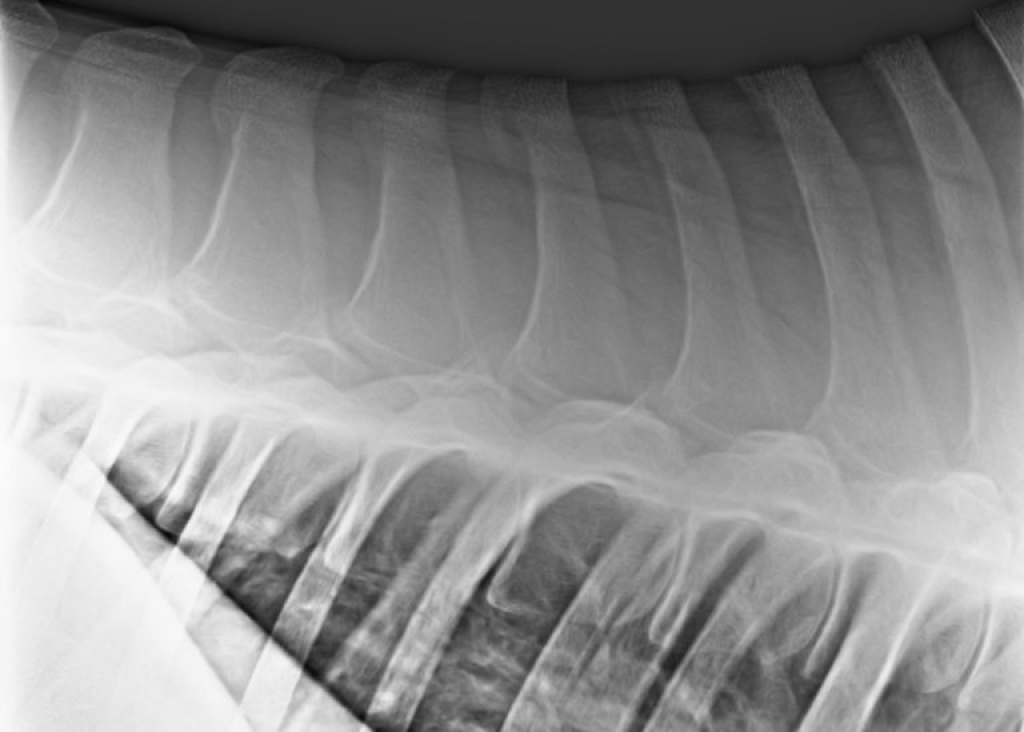

Aan de hand van de klachten, de manier van bewegen en de bevindingen tijdens het onderzoek kunnen we het probleemgebied identificeren. De volgende stap om tot een diagnose te komen is het uitvoeren van diagnostische beeldvorming van het probleemgebied. De hals kunnen we uitgebreid in beeld brengen met behulp van röntgenfoto’s en echografisch onderzoek. De rug is ook met behulp van röntgenfoto’s en echografie te onderzoeken. Het bekken is lastiger in beeld te brengen met röntgenfoto’s omdat het omgeven wordt door een grote hoeveelheid spiermassa. Het bekken is wel echografisch goed te onderzoeken. Dit kan zowel uitwendig als inwendig. Door middel van een inwendig echografisch onderzoek kunnen we ook de tussenwervelschijven van de laatste lendenwervels en het SI gewricht in beeld brengen.

Röntgenopname van de rug